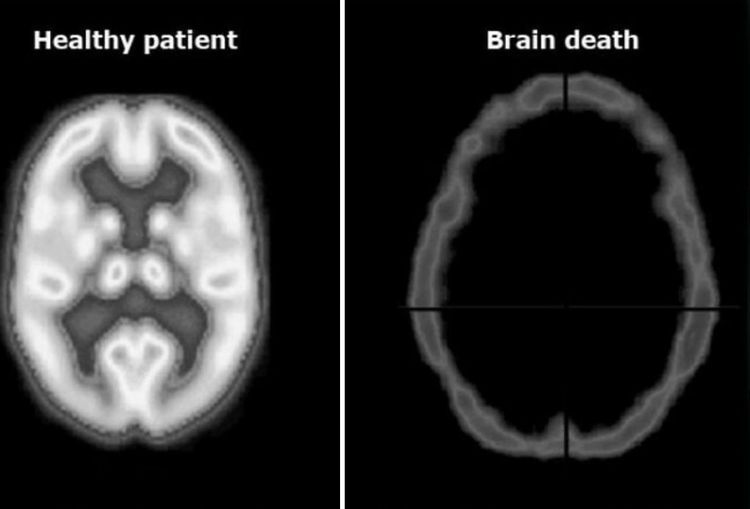

Разница между здоровым и мертвым мозгом пациента, которую можно увидеть при помощи КТ